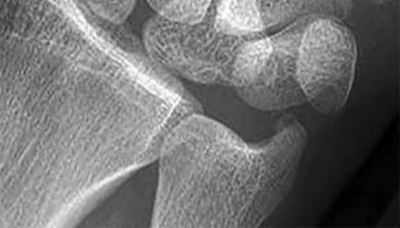

A 20-year-old park ranger trips and falls onto his right wrist with the wrist in extension and pronation. The local urgent care orders both radiographs and a CT, which you review and determine to be normal. The patient complains of ulnar-sided wrist pain. On exam, his tenderness is localized to the fovea. Ulnar deviation also causes him pain. There is no snapping sensation with wrist supination, flexion, and ulnar deviation. He otherwise has 5/5 strength to his first dorsal interosseous muscle with 4mm static two-point discrimination on the ulnar side of the 4th digit. Which of the following injuries is most likely responsible for his symptoms and exam?